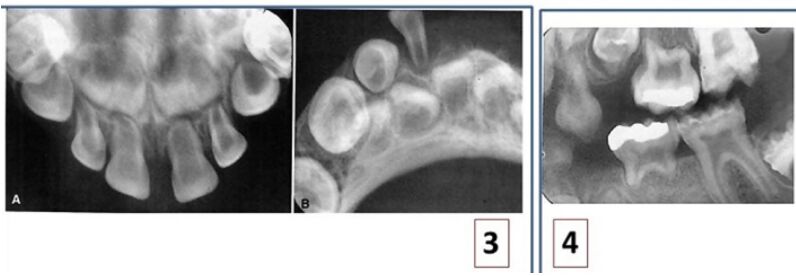

67.病人主訴牙齒容易移位及脫落,其局部根尖片顯示如圖,此病人最可能罹患何種疾病?

(A)局部牙齒發育不良(regional odontodysplasia) (B)第一型牙本質發育不良(dentin dysplasia type I) (C)第二型牙本質發育不良(dentin dysplasia type II) (D)牙本質形成不良(dentinogenesis imperfecta)